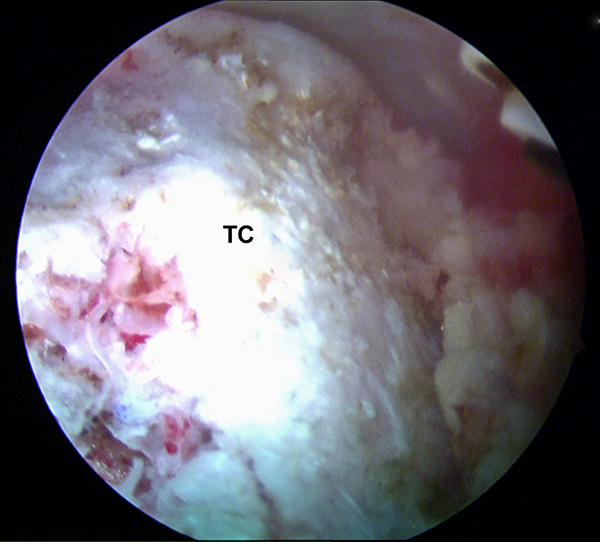

Im nächsten Schritt erfolgt die arthroskopische Darstellung des Tuber calcanei (TC) mit Hilfe des Weichteilshavers und der Radiofrequenzsonde, bis eine gute Übersicht über die knöchernen Strukturen gegeben ist. Damit eine einwandfreie Orientierung und Platzierung des Zielgeräts gewährleistet ist, müssen alle störenden Gewebereste vollständig am Tuber entfernt werden. Zur besseren Übersicht kann es ggf. erforderlich sein, zusätzlich die tiefen paraachillären Zugänge zu verwenden (siehe oben). Unter arthroskopischer Sicht wird der Zielbügel über das posteromediale Portal eingeführt und auf der kranialen Prominenz des Tuber calcanei (TC) platziert. Arastru et al. 15 konnten in biomechanischen Untersuchungen am Kadaver nachweisen, dass die Fixation der FHL-Sehne möglichst weit posterior am Kalkaneus zu einem günstigen Hebelarm mit der besten Kraftentwicklung in der Plantarflexion führt.